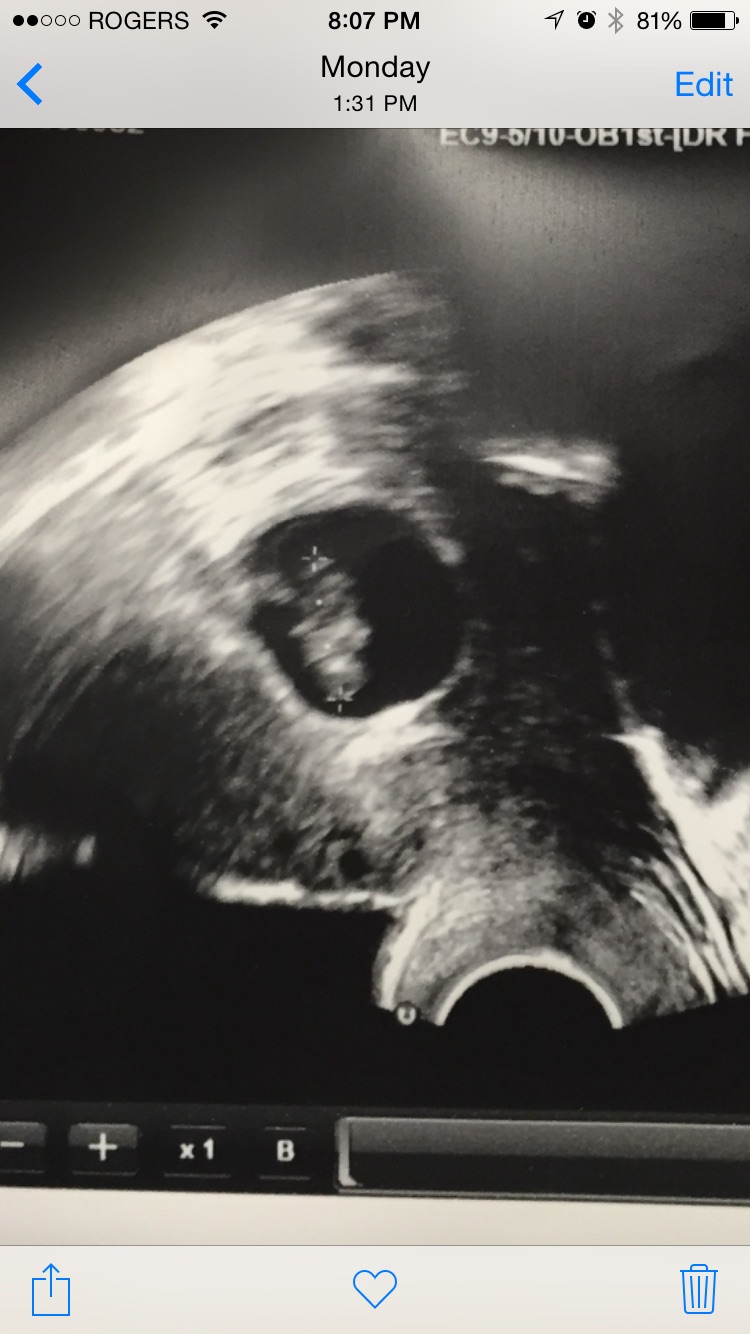

What about mine? this was at 6w6d. It was a transvaginal u/s. I'm 13 weeks now, so I'm not too far from finding out, but I am curious about this Ramzi thing. Thanks!